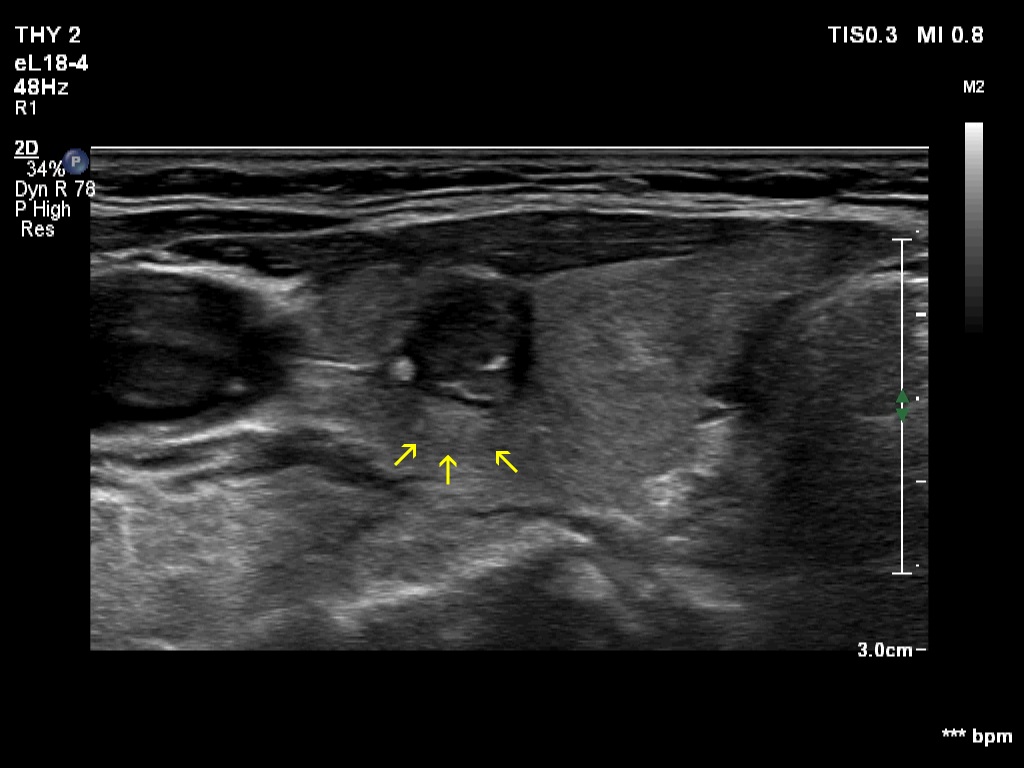

The shape of the nodule - case 2255 (ultrasonographic picture 5b)

Right lobe, transverse scan, enlargement. Yellow arrows point to acoustic amplification caused by the cystic content of the nodule.